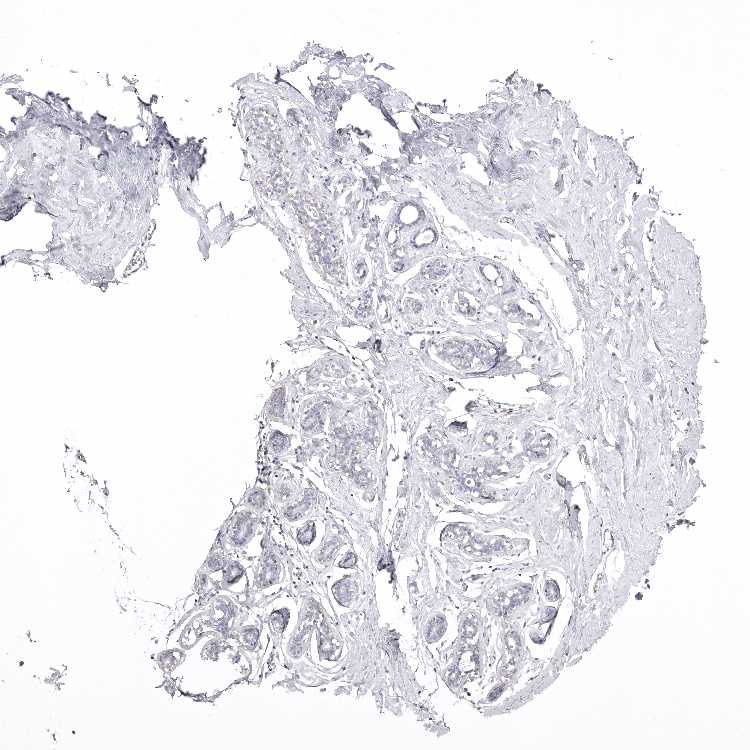

SOFT TISSUE 2 - Antibody stainingi

Antibody staining in the annotated cell types in the current human tissue is reported as not detected, low, medium, or high, based on conventional immunohistochemistry profiling in selected tissues. This score is based on the combination of the staining intensity and fraction of stained cells.

Each image is clickable and will lead to virtual microscopy that enables deeper exploration of all samples and also displays staining intensity scores, fraction scores and subcellular localization as well as patient and tissue information for each sample.

Antibody CAB025366

Fibroblasts Not detected